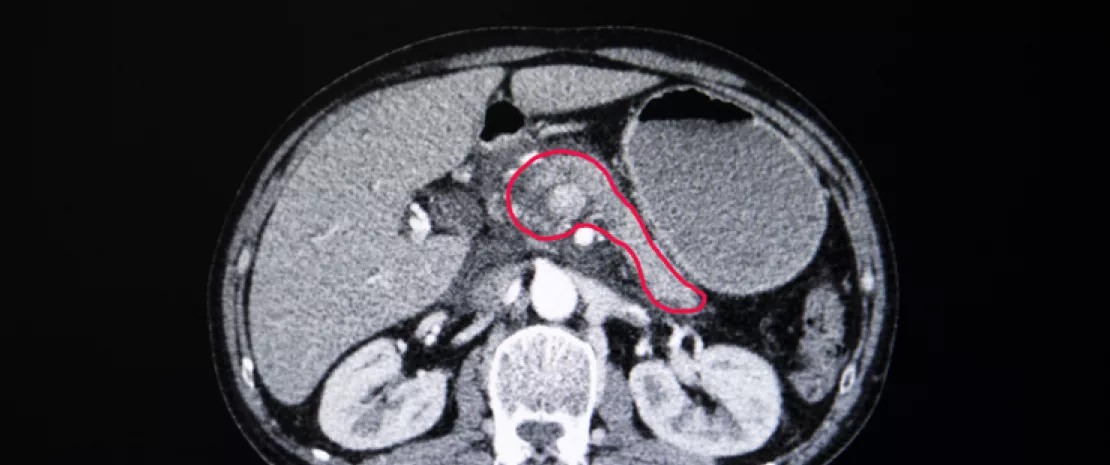

3e cause de décès par cancer aux États-Unis, avec un taux de survie de 9 % à 5 ans, l'adénocarcinome canalaire du pancréas (PDAC)est un cancer redouté. Des études précédentes ont montré que le microbiote tumoral des patients PDAC contient des bactéries normalement présentes dans le tractus gastro-intestinal supérieur, celles-ci auraient donc migré du duodénum. Si tel est le cas, le liquide duodénal pourrait constituer un bio-échantillon d’intérêt pour caractériser les profils microbiens des patients atteints ou à risque de PDAC. D’où cette étude cas-témoins monocentrique comparant les profils bactériens et fongiques du liquide duodénal de patients subissant une endoscopie : 134 témoins avec un pancréas normal, 98 patients avec kyste(s) pancréatique(s) et 74 patients avec un PDAC.